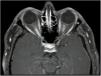

Neuritis óptica (figs. 2 y 3), que suele ser extensa, con compromiso del quiasma óptico o más del 50% de la longitud del nervio óptico y con un compromiso de moderado a severo de la agudeza visual.